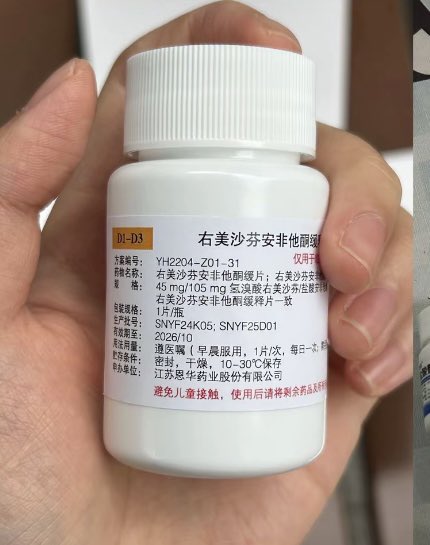

关于后藤提到过的“反解离”

首先,从定义上讲,“反解离(anti-dissociative)”并不是一个标准的医学术语或者广泛认同的药理学分类。在正规资料,比如医学文献、维基百科、精神药理学教科书中,目前并没有“反解离药物”这个正式概念。

看上去像是为了描述某类特定效应而创造的术语(可能是nmda受体活性增强),用来对抗因NMDA受体拮抗剂(比如氯胺酮、DXM、PCP等)引发的解离体验(dissociation)。

那么更常见的是将其归入认知增强剂(cognitive enhancers),特别是改善认知连接性(connectivity)和现实感知(reality testing)的类型。

但其实在药理学上,单纯用“受体激动剂”来逆转“受体拮抗剂”的效应,有时会导致过度激活。

对于NMDA受体而言,过强的NMDA活化本身就与兴奋性毒性(excitotoxicity)和精神病样症状(psychotomimetic effects)有关,比如谷氨酸风暴可以引发严重的焦虑、妄想、乃至癫痫。

也就是说,简单地“激动-解除拮抗”在中枢神经系统是很危险的做法,尤其是对于易感个体(如有精神分裂素质的人)。

科学的处理方式一般是通过更细致的调节,比如微调NMDA/AMPA平衡、调节其他辅助途径(如GABA、5-HT、mGluR受体),而不是简单粗暴地用“NMDA增强剂”去顶回去。

而临床处理药物中毒中,其实医生更常用的做法是保守、支持性的治疗,比如补液,促进代谢,必要时镇静,以及监测生命体征防治并发症。

药物拮抗与受体激动之间,往往牵扯到的是复杂的适应性变化(receptor upregulation/downregulation),

不是简单的“给多一点刺激就能抵消”的关系